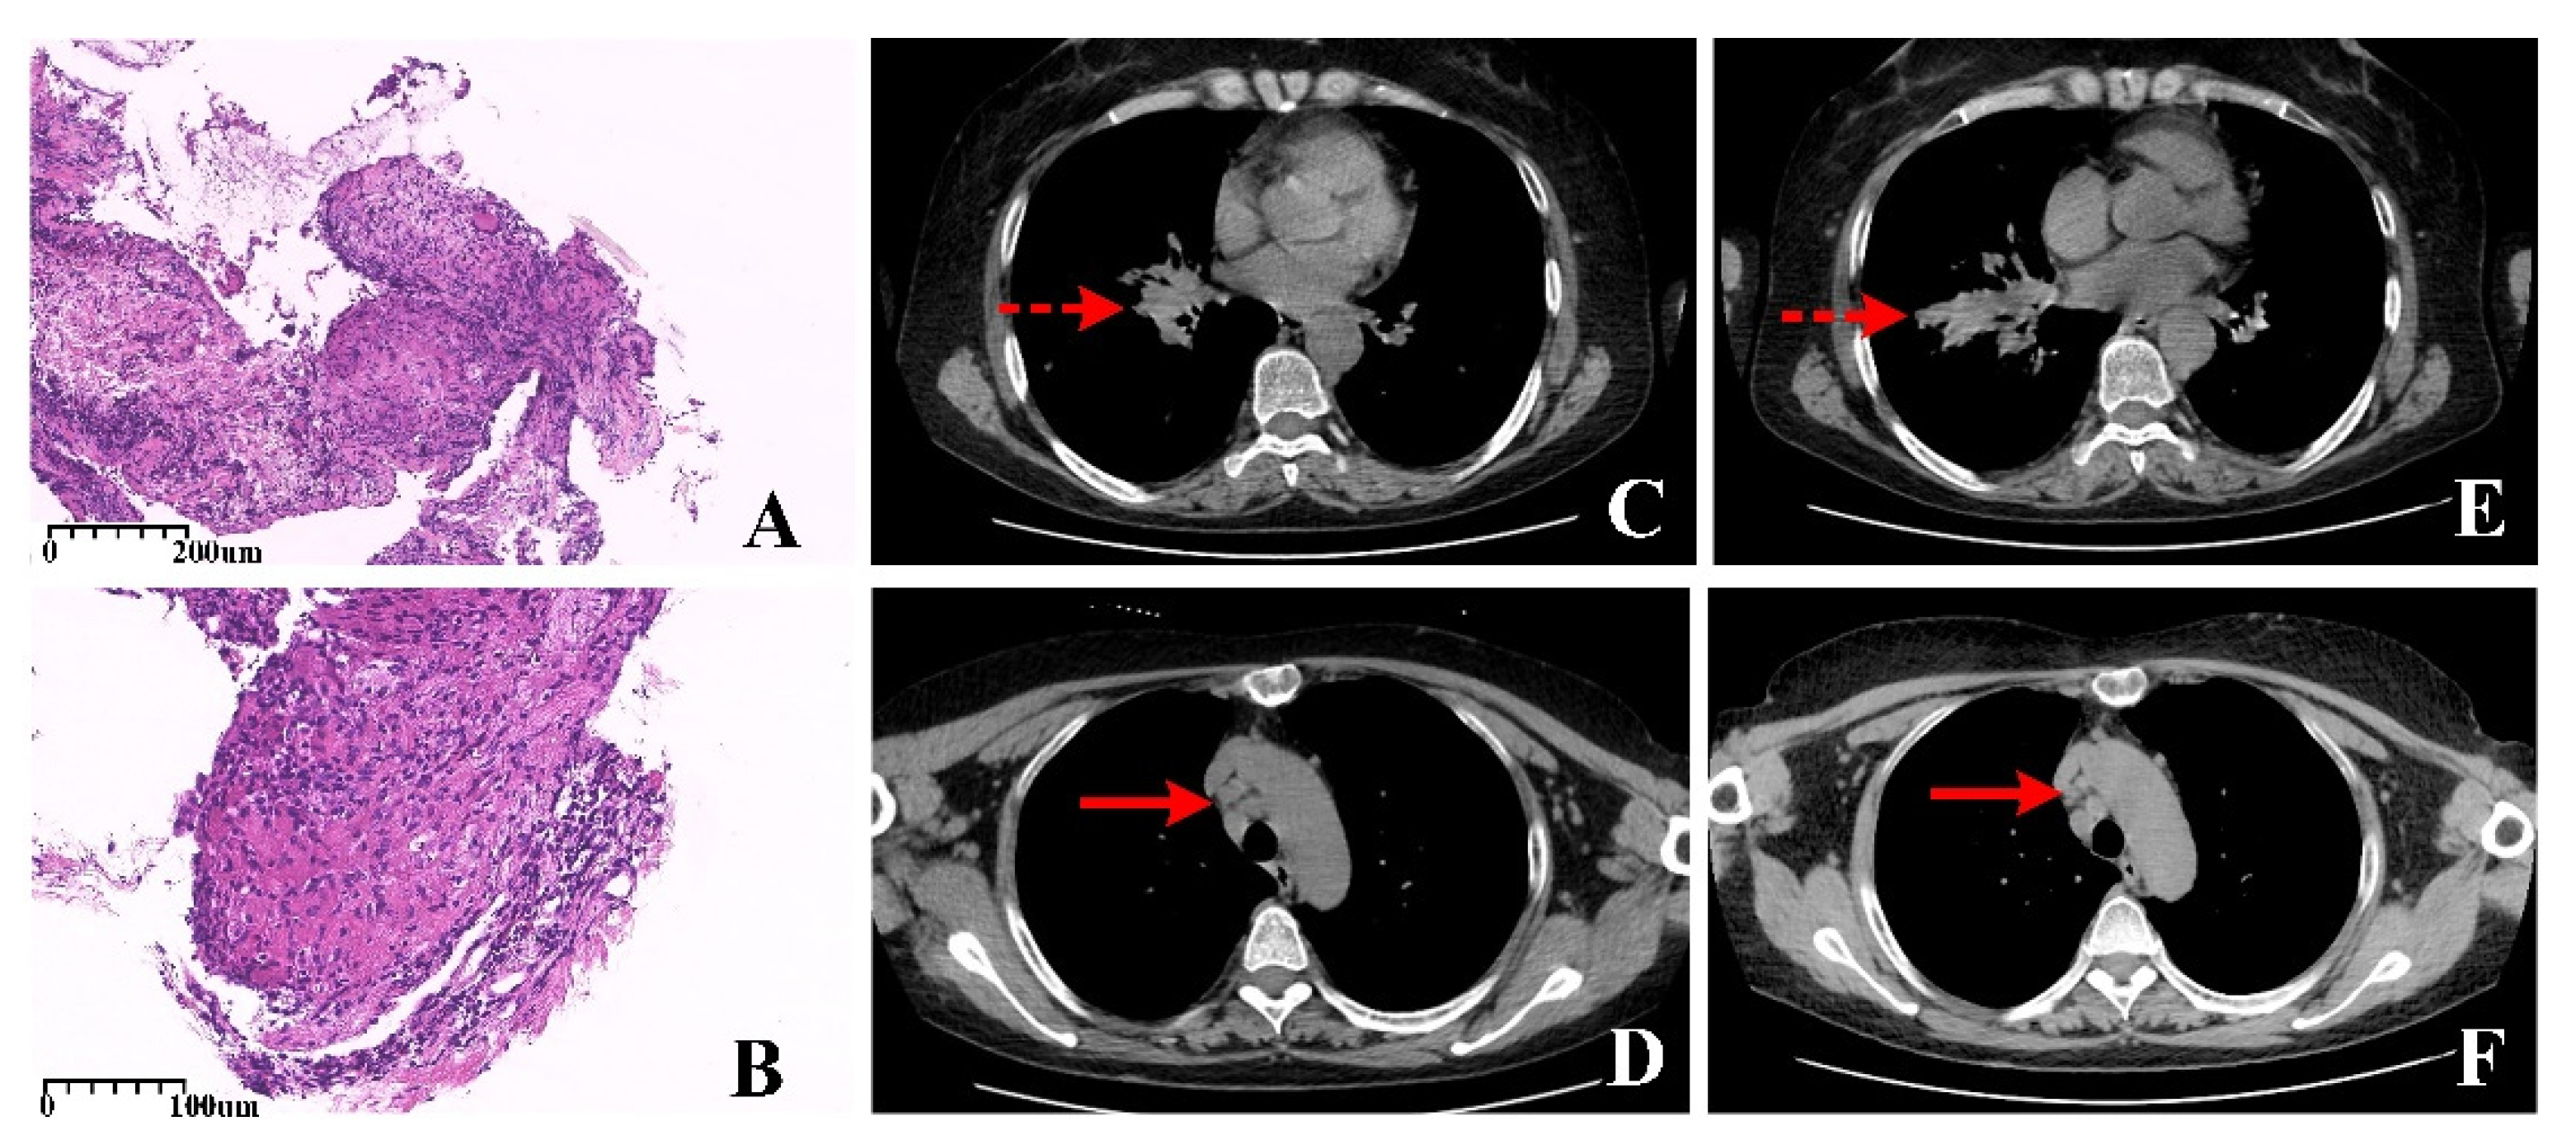

画像診断2020年増刊号(Vol.40 No.4) 似て非なる画像“The。画像診断2025年8月号 Vol.45 No.9: 治療に役立つ頭頸部画像診断。m3電子書籍 | 画像診断 Vol.40 No.4(2020年増刊号)似て非なる。「似て非なる画像\"The mimickers\"の鑑別診断」松木 充やや使用感はありますが、書き込みなどはなく、中は綺麗な状態です。Sarcoidosis Mimicking Primary Lung Cancer on 99mTc-3PRGD2。(^o^)#松木充 #松木_充 #本 #自然/医療・薬学・健康

• Sarcoidosis Mimicking Primary Lung Cancer on 99mTc-3PRGD2